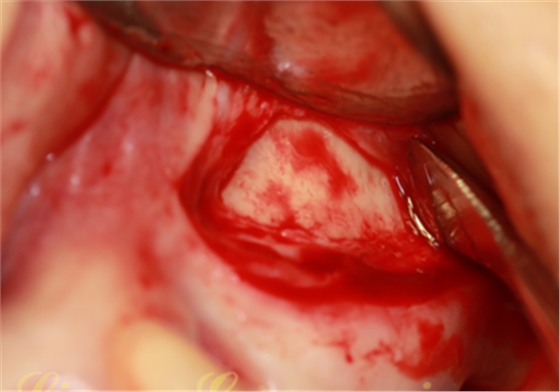

竇底骨量實在太有限,小于3mm骨高度,建議先提升植骨,二期種植。不種植就無需牙槽嵴頂切口、大翻瓣,頰側(cè)改良式切口:切口小,創(chuàng)傷小、術(shù)后反應(yīng)輕。

開孔鉆配合停止環(huán),停止環(huán)從1mm逐漸增加,直到有落空感為止。連接水壓系統(tǒng),連接一次性注射器,1mm生理鹽水,橡皮堵緊緊堵住孔,輕壓將生理鹽水推入,在沒有開窗之前已經(jīng)將頰側(cè)上頜竇膜剝離

第三代產(chǎn)品中的開窗鉆中間增加了柱形定位柱,比周邊的齒狀邊緣長出1mm,剛好可以插入開孔鉆制備的小孔,切割時不會滑動。由于頰側(cè)上頜竇膜已經(jīng)被水壓剝離,所以大膽切下去,幾秒鐘完成開窗。